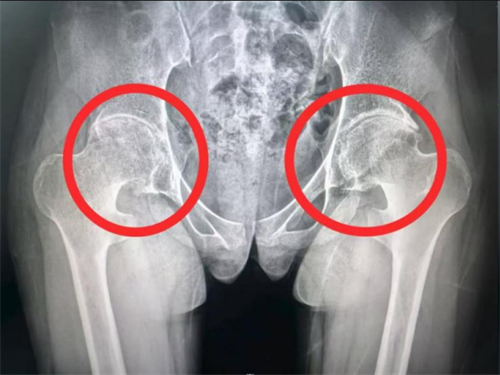

X片显示双侧髋关节间隙严重狭窄、软骨溶解,髋关节屈曲挛缩畸形